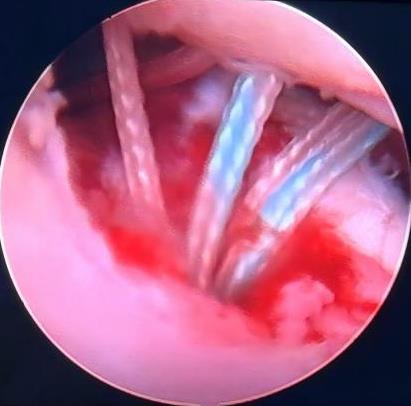

摘要:目的 探讨常规切开Latarjet手术、关节镜下Latarjet手术、关节镜下Bankart修复联合Remplissage手术在肩关节复发性前脱位(RASD)合并肩胛骨关节盂骨缺损 > 15%及啮合性Hill-Sachs损伤中的应用效果及安全性。方法 回顾性分析该院2022年1月-2024年12月收治的65例RASD合并肩胛骨关节盂骨缺损15%~25%及啮合性Hill-Sachs损伤患者的临床资料,根据手术方法的不同,分成A、B和C组;其中,A组实施常规切开Latarjet手术(n = 18),B组实施关节镜下Latarjet手术(n = 21),C组实施关节镜下Bankart修复联合Remplissage手术(n = 26)。比较3组患者手术情况、手术前后相关量表评分[视觉模拟评分法(VAS)、Constant-Murley肩关节评分和加州大学洛杉矶分校(UCLA)肩关节评分等]和肩关节活动度,以及术后并发症和复发情况。结果 手术时间:B组长于A组和C组(P < 0.05),A组长于C组(P < 0.05)。术中出血量和住院时间:A组多于或长于B组和C组(P < 0.05),B组多于或长于C组(P < 0.05)。3组疼痛VAS评分:术后1、6和12个月都低于同组术前(P < 0.05)。术后1和6个月疼痛VAS评分:A组均高于B组和C组同期(P < 0.05)。术后1个月疼痛VAS评分:B组高于C组(P < 0.05)。术后12个月疼痛VAS评分:3组差异不明显(P > 0.05)。比之同组术前,A组术后6和12个月,B组和C组术后1、6和12个月,UCLA肩关节评分均明显升高(P < 0.05)。术后1个月UCLA肩关节评分:A组低于B组和C组(P < 0.05),B组低于C组(P < 0.05)。术后6和12个月UCLA肩关节评分:3组患者差异均不明显(P > 0.05)。比之同组术前,A组术后6和12个月,B组和C组术后1、6和12个月Constant-Murley评分均明显升高(P < 0.05)。术后1个月Constant-Murley肩关节评分:A组低于B组和C组(P < 0.05)。术后6和12个月Constant-Murley肩关节评分:3组患者无明显差异(P > 0.05)。3组患者前屈上举活动度:术后12个月都大于同组术前(P < 0.05)。术后12个月前屈上举活动度:3组患者无明显差异(P > 0.05)。术前、术后12个月体侧外旋、外展90°外旋活动度:A组和B组组内和同期组间均无明显差异(P > 0.05)。C组体侧外旋、外展90°外旋活动度:术后12个月小于术前(P < 0.05)。术后12个月体侧外旋、外展90°外旋活动度:A组和B组均大于C组(P < 0.05)。术后并发症发生率和复发率:3组患者无明显差异(P > 0.05)。结论 常规切开Latarjet手术、关节镜下Latarjet手术、关节镜下Bankart修复联合Remplissage手术治疗RASD合并肩胛骨关节盂骨缺损15%~25%及啮合性Hill-Sachs损伤,均能有效改善肩关节功能及缓解疼痛,但两种肩关节镜手术的创伤更小,术后恢复更快。